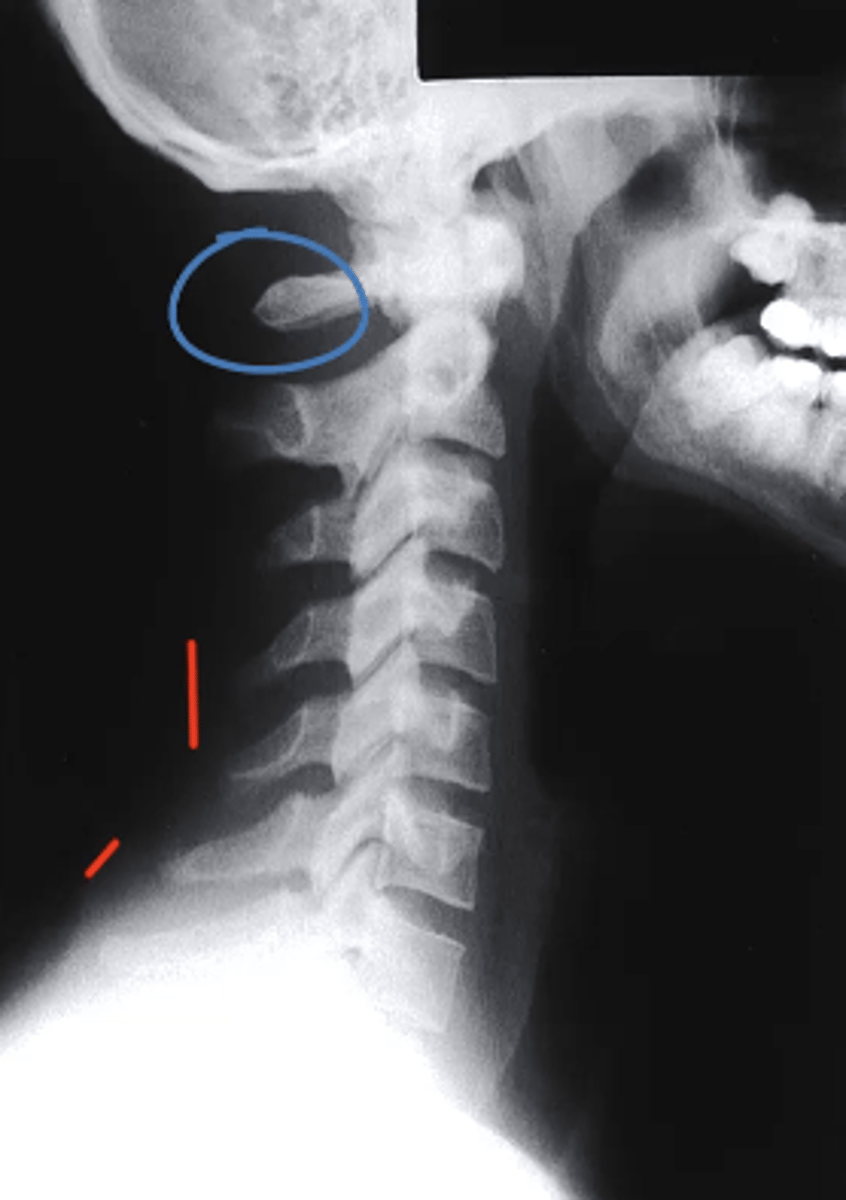

Posterior Arch of C1

What structure is circled in blue?

a. Dens

b. Spinous Process of C2

c. Spinous Process of C3

d. Posterior Arch of C1

D

which structure corresponds with the retropharyngeal space?

a. Line 1

b. D

c. Line 3

d. E

E

which structure corresponds with the retrotracheal space?

Between Line 2 and Line 3

Where would the spinal cord run in this image?

a. Between line 1 and Line 2

b. Between Line 3 and Line 1

c. Between Line 1 and the soft tissue

d. Between Line 2 and Line 3

what can be identified on a lateral view of the C spine?

-arches of C1

-Dens

-vertebral bodies of C2-C7

-articular pillars and lamina

-IVD spaces from C2-C3 through C6-C7

-spinous processes

-transverse processes

-facet joint surfaces